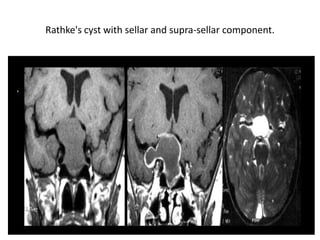

Rathke's cleft cyst (coronal T2-, coronal and sagittal T1-weighted scans).

Rathke's cleft cyst arise from the craniopharyngeal duct (Rathke's, s pouch) (An epithelial

structures connect nasopharynx with the 3rd ventricle , involutes during fetal life).

Rathke's cleft cyst

Rathke's cleft cyst(Pre and post-contrast images).

These T1, T2 and T1-weighted images after gadolinium demonstrate another Rathke's cleft

cyst located in the pituitary gland. Unlike the normal pituitary tissue and pituitary stalk it does

not enhance after the administration of intravenous contrast. The normal pituitary tissue is

compressed and displaced far to the left. It is important to recognize this as it could be

mistaken for an enhancing component of the cystic mass.

Rathke's cyst with sellar and supra-sellar component.